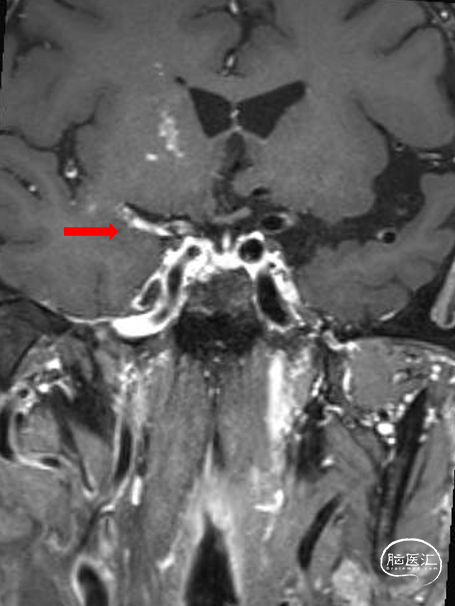

颅脑斑块分析:右侧大脑中动脉M1-3段混合斑块形成(易损斑块及少许血栓附着),管腔重度狭窄。

T1增强

T2

斑块分析:左侧大脑中动脉近中段M1段重度狭窄、M1远段-M2分支起始处混合斑块形成,局部管腔闭塞;远端分支较对侧明显减少。

T2

T1增强